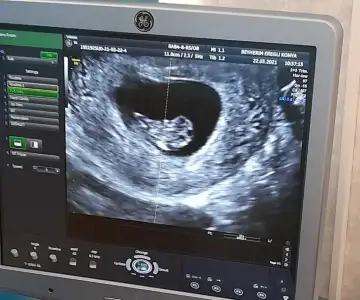

Merhaba canım ilk bebegimi doğru tahmin etmiştim ikinciye hamile kaldım şimdilik bı tane resim var telefonumda ekrandan çekmiştim çıktısı yanımda değil bı bakabilirmisin cinsiyeti acaba ne.9+5burda.

Eklentiler

• IMG_20210326_092231.webp

IMG_20210326_092231.webp

53,2 KB · Görüntüleme: 77